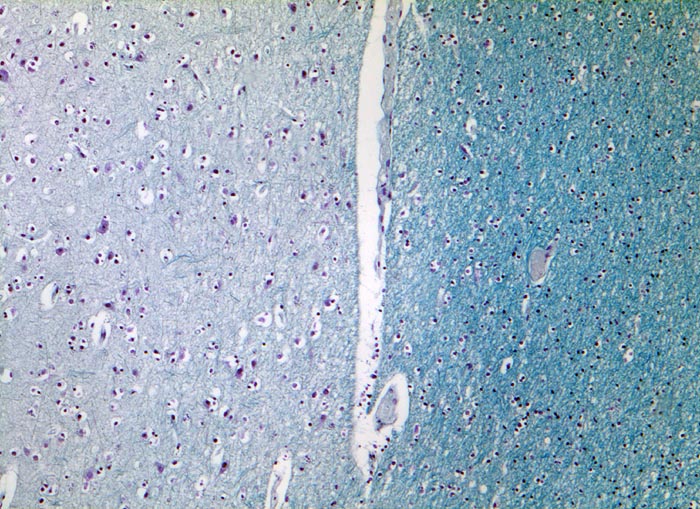

Links im Bild die in der Markscheidenfärbung helle Hirnrinde mit grösseren Neuronen und Oligodendrozyten umgeben von einem Halo. Rechts das in der Markscheidenfärbung dunkel erscheinende Mark mit dichter liegenden Oligodendrozyten. In der weissen Substanz fehlen die Neurone.